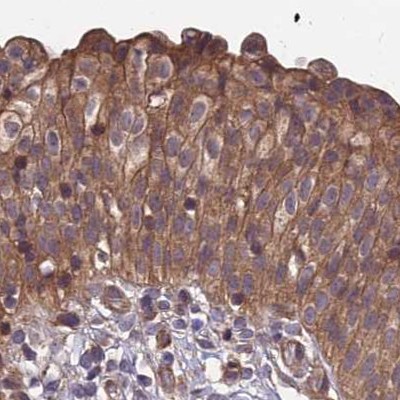

Immunohistochemical staining of human colon, kidney, testis and urinary bladder using Anti-MKKS antibody HPA041071 (A) shows similar protein distribution across tissues to independent antibody HPA044233 (B).